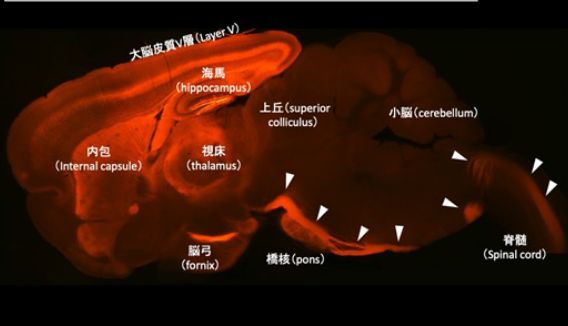

脳をつなぐコードを遺伝子から読み解く